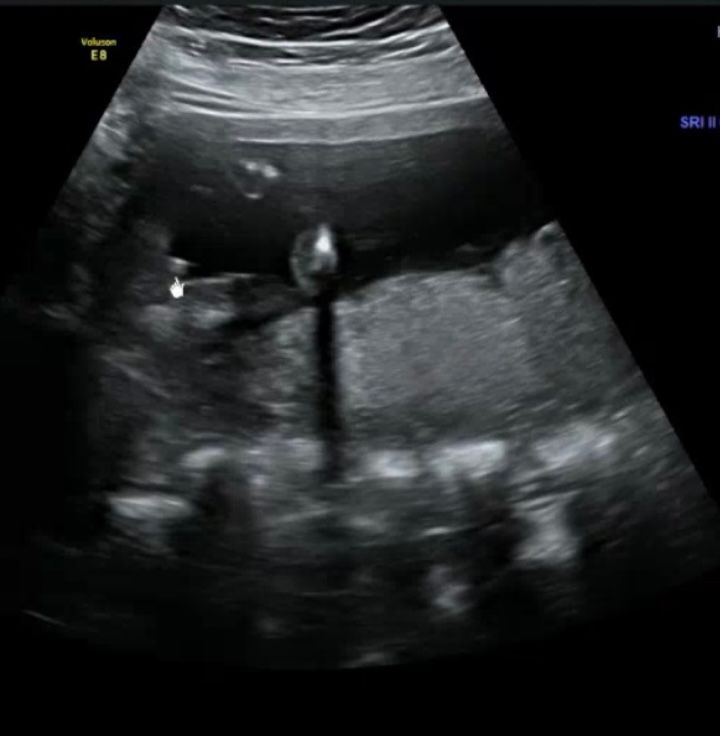

Ходила в 15 недель, сказали мальчик (на фото сбоку ножки, справа - писюн). Ходила сегодня, 17.4 нед, намёка на писюна нет, по УЗИ такая картинка (взяла из интернета), врач сказал в девочка 🤦♀️Кто мог ошибиться? Могли же просто писюн не увидеть сегодня,или никаких нет надежд на девочку? Покажите подскажите фото УЗИ с 17-18 недель, и кто у вас?

На первом фото, простите, ну прям писюнище для такого срока)) Скорее всего это так пуповина сложена была, бликовала. А на втором прям девочка.

Ого, на первом фото такой четкий писюн, не похож на пуповину совсем. Куда он тогда делся?🤔у нас у дочки в 15 недель было точь-в-точь как на втором фото.

Пуповина может показаться письмом. Вторая фотка чётче, а на ней- кофейное зернышко. Похоже реально девочка( у моей так и было)